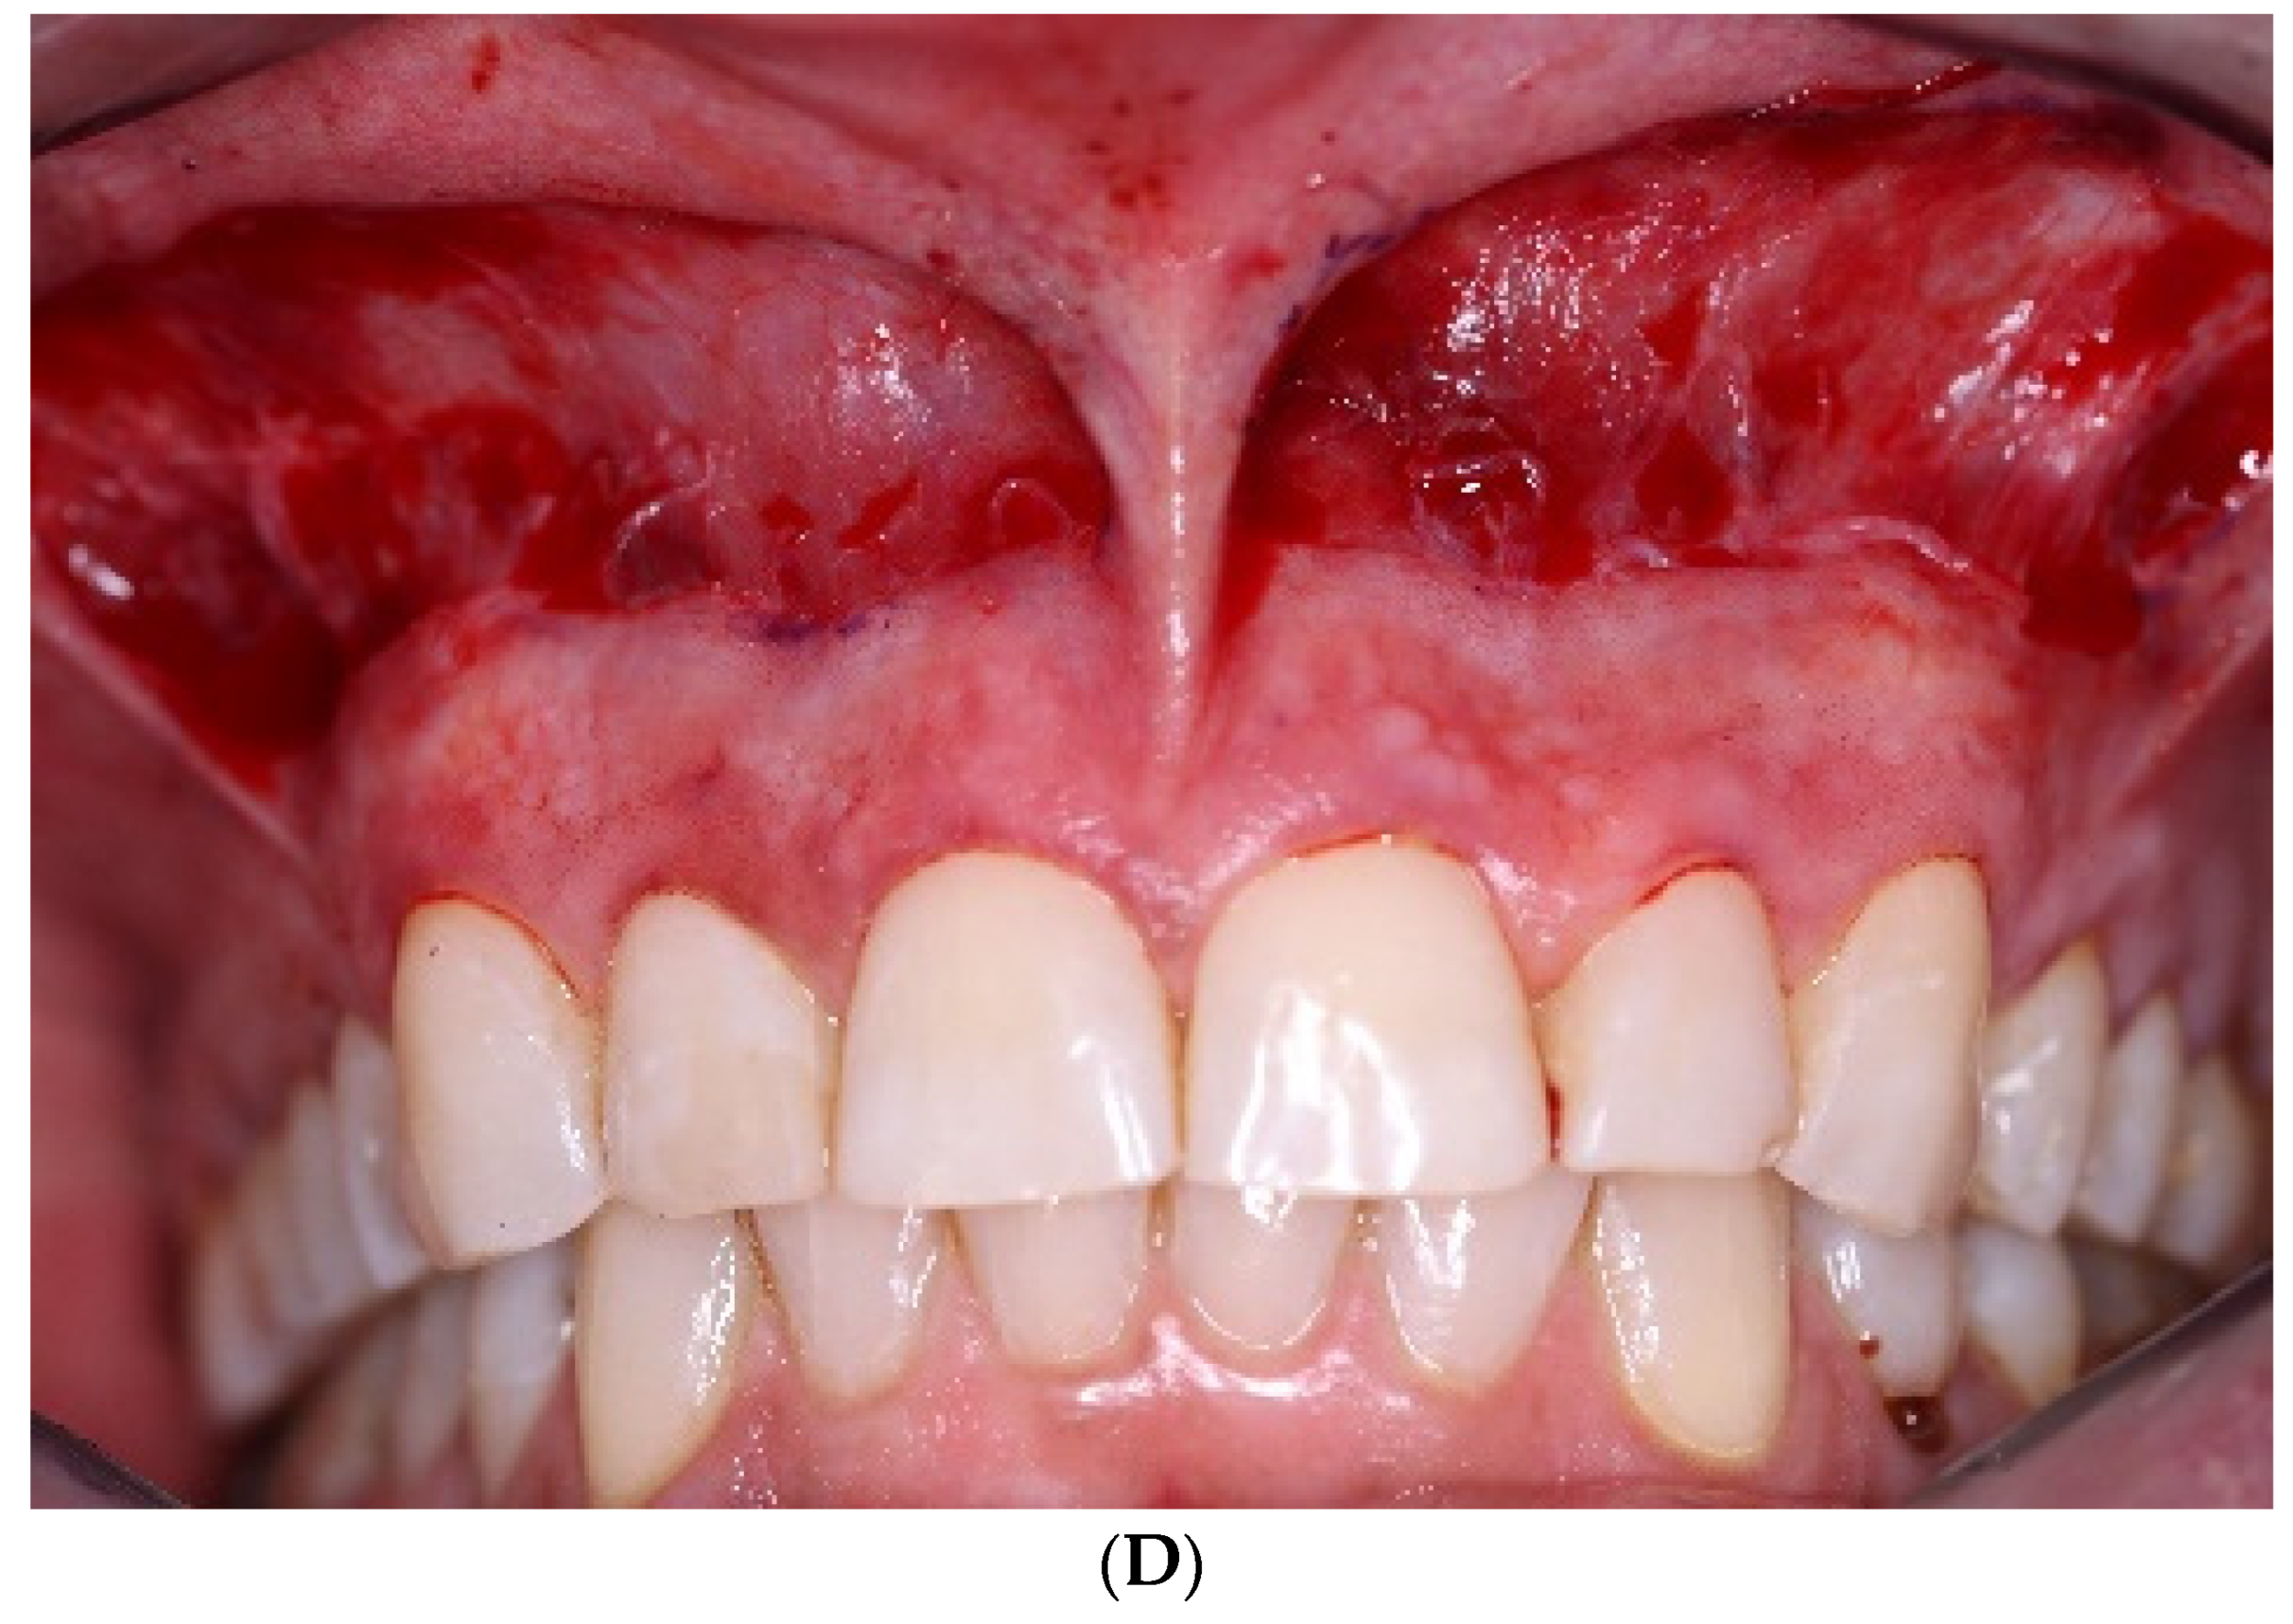

2. Case Presentation